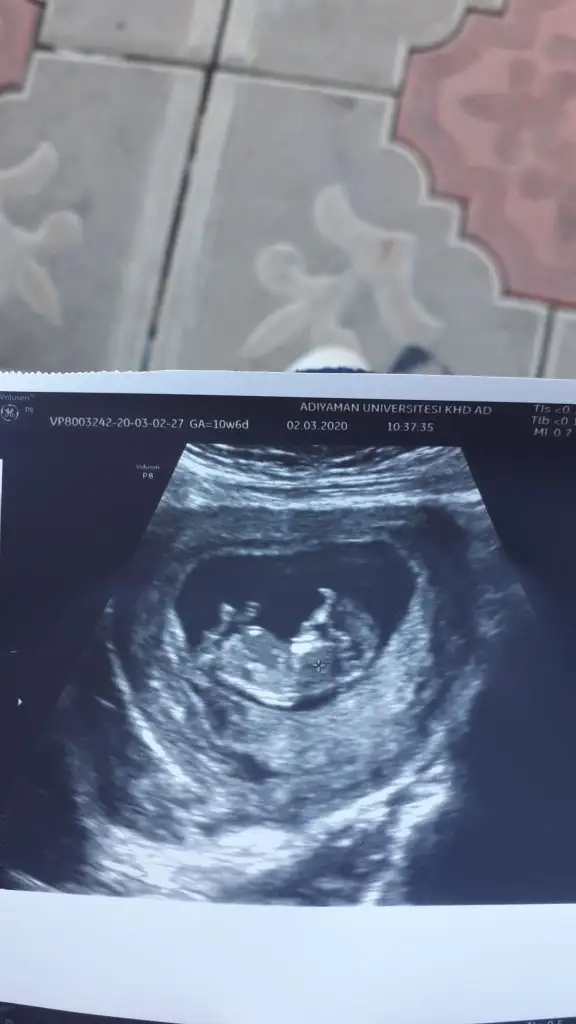

dr soylemeden siz gorun genital nub teorisi ( bebegin cinsiyeti)

Senin nubu çizdim cnm arkadaşında çizdim pipide vardı arkadaş pipi olsa söylemezmi deyince bende diğer 10 ve 11 haftasndaki tahminim devam dedim çok istiyordu pipiyi dr görmedi deyince ne kadar geç ögrenise dedim yoksa baya baya pipiydi çizdiğim usg 😊 seninkinide çizdim parelel görünüyor tabi pozisyonu nubu bazen değiştiyor. umarım 31 yanlış tahminim var arasında olmazsın onlar beni yanıtan usgler 😊